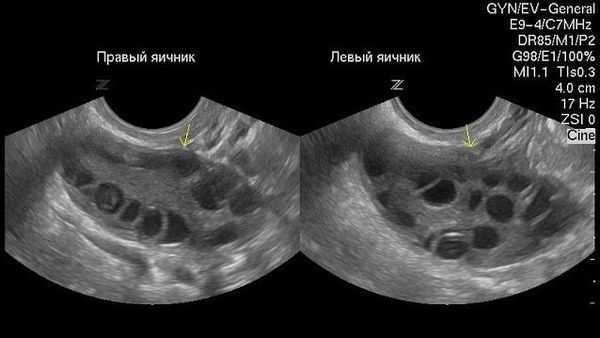

• ФК:

о Кистозный очаг внутри яичника, имеющий тонкие стенки

о При допплерографии усиления кровотока не определяется

о Как правило, возникает в первой половине менструального цикла или после несостоявшейся овуляции

(Слева) УЗИ органов малого таза: типичная картина анэхогеной функциональной кисты с окружающей паренхимой яичника (отмечена калиперами).

(Справа) Функциональные кисты яичника могут увеличиваться, тогда окружающая паренхима яичника сжимается до тонкого ободка. Когда имеются такие проявления, как тазовая боль, необходимо использовать импульсную допплерографию для оценки форм колебаний артериального и венозного кровотоков.